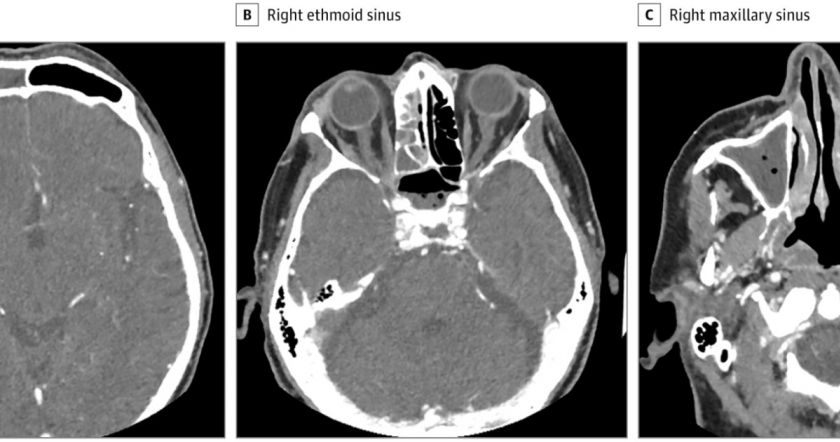

Համակարգչային տոմոգրաֆիան անմիջապես ցույց է տվել ուժգին ցավի աղբյուրը՝ աչքի շուրջ գտնվող ոսկրի սինուսի բորբոքումը։ Դեպքն այնքան լուրջ էր, որ ոսկորն սկսել էր քայքայվել։ Անհրաժեշտ է եղել արտակարգ վիրահատություն անցկացնելոու և խոռոչը հնարավորինս մաքրելու։ Թվում էր, թե վիրահատությունը կօգնի, սակայն քիչ ժամանակ անց ցավը կրկին սկսվեց, իսկ տեսողությունը՝ վատացավ։

Բորբոքման տեղում հայտնաբերվեց Streptococcus constellatus բակտերիան։ Վերջինս հիմնականում բնակվում է աղիներում և բերանի խոռոչում, սակայն մարմնի այլ հատվածնեում հայտնվելիս բորբոքումներ է առաջացնում։ Դրա դեմ չեն կարողանում պայքարել անգամ հակաբիոտիկները։